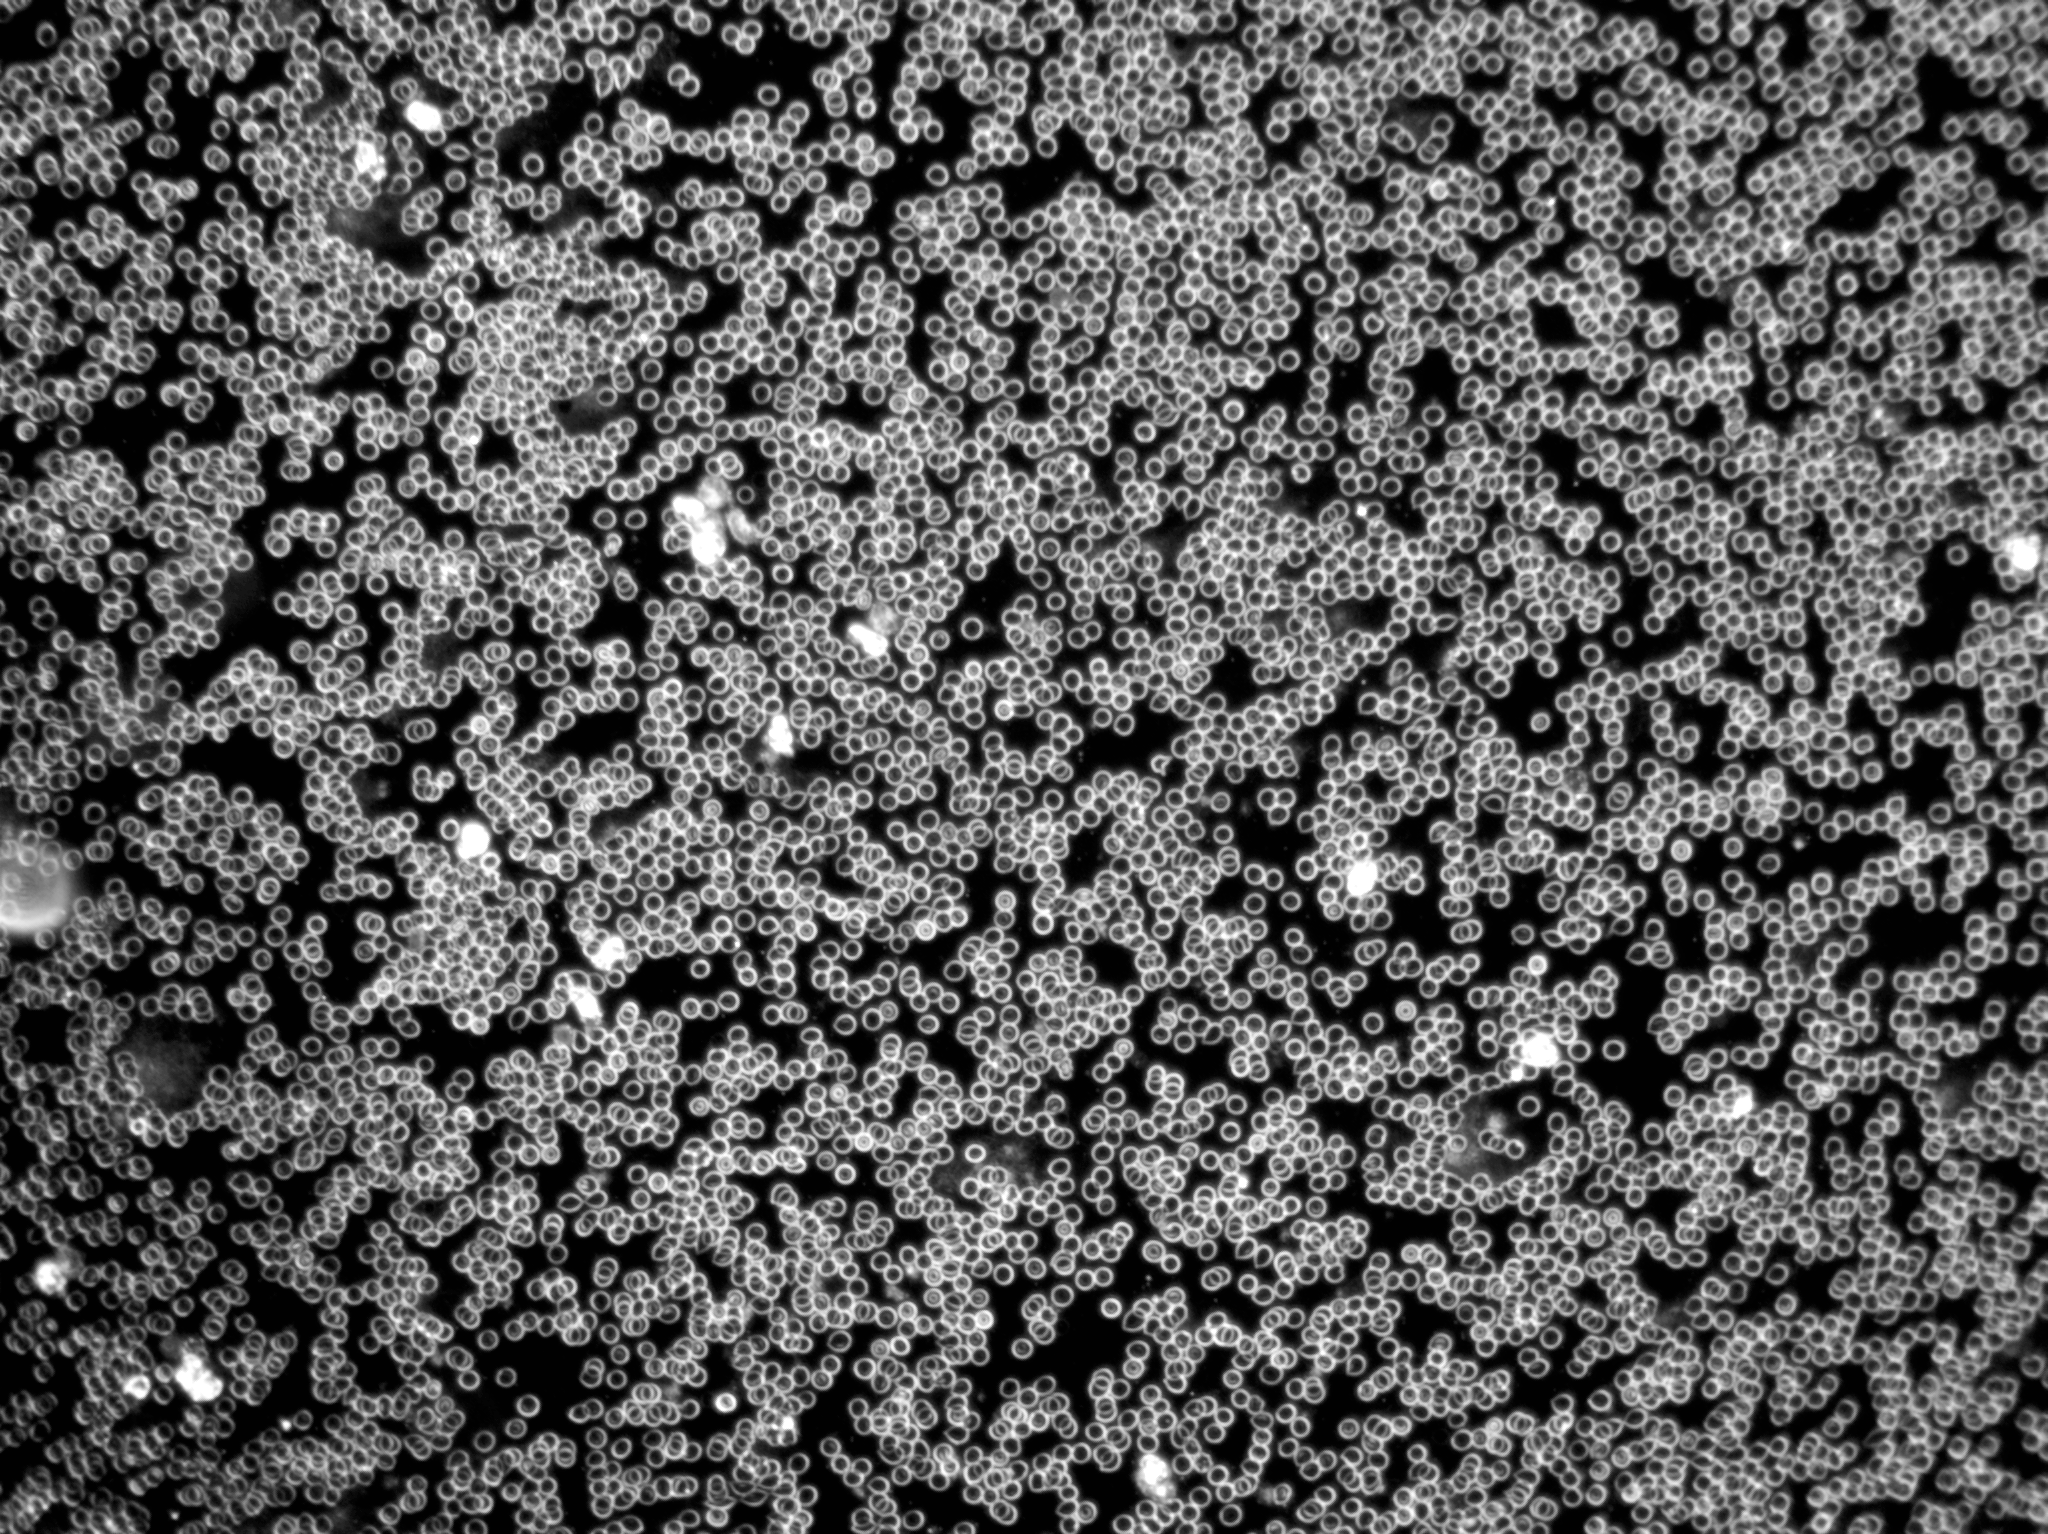

Vitalblutanalyse 1. Tag

Dichtem Vorkommen von kreisförmigen Zellen. Leichte Aggregationen sichtbar, aber keine eindeutigen abnormalen Formen oder Parasiten erkennbar. Weitfeld-Okulare mit 10-facher Vergrößerung & 10x Objektiv